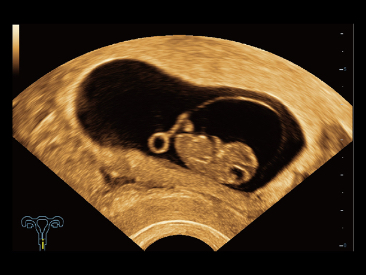

As well as the premium level image quality, Resona 7 also enhances clinical research capabilities with the revolutionary V Flow for vascular hemodynamic evaluation, and the most intelligent plane acquisition from 3D datasets for fetal CNS diagnosis. Combining the most intuitive gesture-based multi-touch operation and all the essential clinical features, Resona 7 is truly leading new waves in ultrasound innovation.